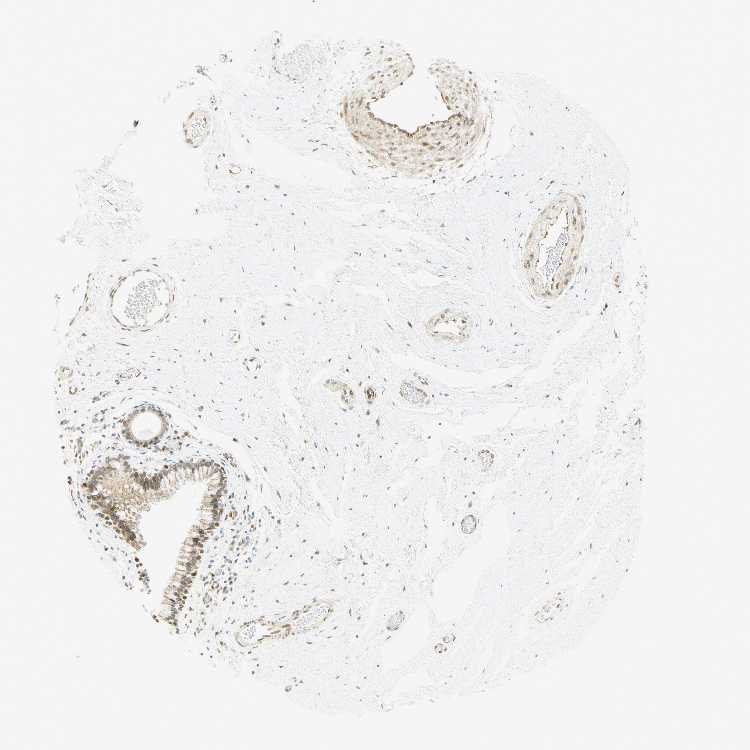

TISSUE PRIMARY DATA NASOPHARYNX Show tissue menu

Nasopharynx

NASOPHARYNX - Antibody stainingi

Antibody staining in the annotated cell types in the current human tissue is reported as not detected, low, medium, or high, based on conventional immunohistochemistry profiling in selected tissues. This score is based on the combination of the staining intensity and fraction of stained cells.

Each image is clickable and will lead to virtual microscopy that enables deeper exploration of all samples and also displays staining intensity scores, fraction scores and subcellular localization as well as patient and tissue information for each sample.

Antibody HPA008003Antibody CAB000329Antibody CAB019308

Respiratory epithelial cells HighHighHigh